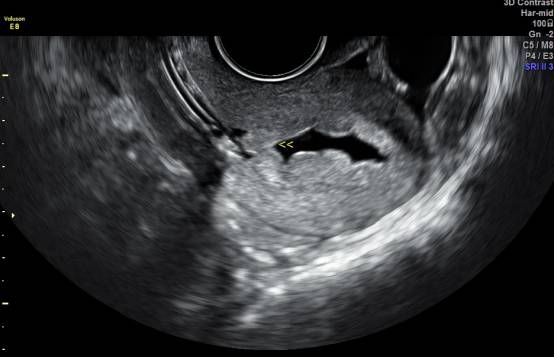

宫腔水造影显示宫腔息肉

子宫输卵管造影检查,是女性不孕症常规检查项目之一。然而,部分女性却从心理上对它有点儿打怵:传统的子宫输卵管造影检查是在X线下进行的,身体难免会遭受到射线辐射,短时间内不宜怀孕,为弥补这一不足,医院引进子宫输卵管声学造影(HyCoSy)技术,利用超声成像技术使得子宫和输卵管清晰显影。济宁市第一人民医院超声科主任吕镔介绍,该技术具有高清晰的图像分辨,对于输卵管通畅性评价更直观,准确性高,无辐射、无损伤。而且,患者在检查前无需做特殊准备,造影剂在患者体内停留时间短,安全性高,检查完当月即可备孕。

“操作中将造影剂经置入宫腔的导管注入子宫腔和输卵管腔,显示子宫腔和输卵管腔的形态、位置,发现宫腔和输卵管内病变、畸形以及评估输卵管通畅度。超声造影剂对人体无毒害,进入体内后迅速排出,对生殖系统无影响,超声造影技术操作简单、创伤轻微、安全、重复性好及检验输卵管通畅度的高准确性等优势,子宫输卵管超声造影也可使轻度粘连的输卵管得到疏通。”熟练开展该技术的医生陈谦谦介绍,若结果为输卵管通畅,下一月经周期即可实施助孕方案,可能使患者受孕时间提前,故对生殖时间窗影响小。经阴道超声造影探头的出现使患者无需憋尿、不受肥胖及肠道气体的干扰,从而显著提高了诊断的准确率。

概述:子宫输卵管超声造影是指通过宫腔置管向宫腔内注入超声微泡造影剂的混悬液,实时显示宫腔形态、输卵管走形以及盆腔弥散情况,从而评估输卵管通畅性以及宫腔疾病、盆腔粘连等情况。